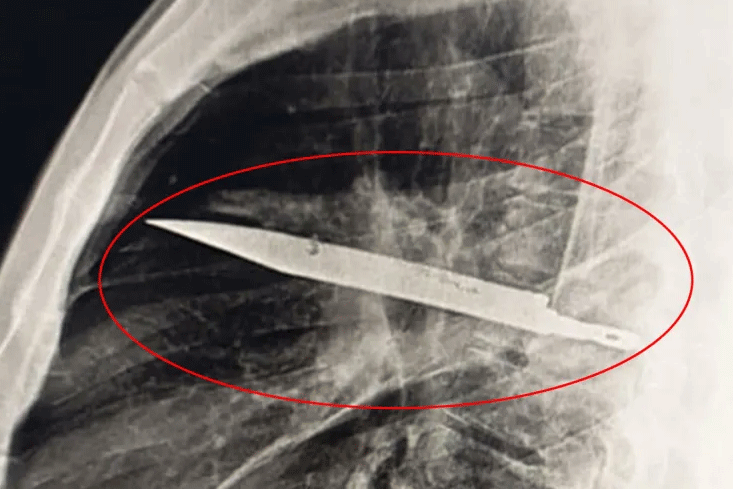

Người đàn ông không hay biết có lưỡi dao lớn mắc kẹt trong ngực suốt 8 năm

TANZANIA - Các bác sĩ đã rất sốc khi phát hiện lưỡi dao lớn mắc kẹt trong ngực một người đàn ông suốt 8 năm mà không hề gây ra triệu chứng nghiêm trọng nào.